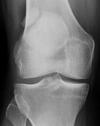

* In infantile Blount disease, excess medial pressure (such as in early walkers who are obese and have physiologic varus alignment) produces an osteochondrosis of the physis and adjacent epiphysis that may progress to a physeal bar. * In adolescent Blount disease, a varus moment at the knee during the stance phase of gait further inhibits medial physeal growth according to the Hueter-Volkmann principle (compression results in decreased growth of the physis). ## Footnote Infantile Blount's disease is progressive pathologic genu varum centered at the tibia in children 2 to 5 years of age. Diagnosis is suspected clinically with presence of a genu varum/flexion/internal rotation deformity and confirmed radiographically with an increased metaphyseal-diaphyseal angle. Xrays shows The severe depression of the proximal medial tibial epiphysis is most consistent with the diagnosis of neglected infantile Blount's disease. Blount's disease in adolescents produces a deformity in the metaphyseal region.